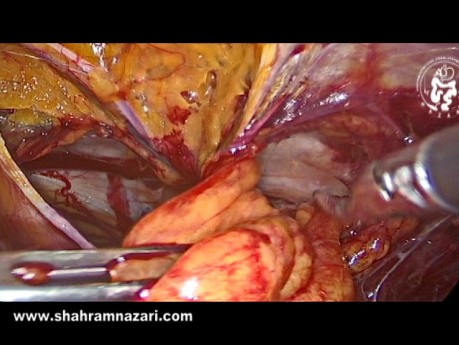

OrthoProcédure - Arthroplastie de la Tête Radiale

OrthoProcédure - Arthroplastie de la Tête Radiale.

Shahram Nazari

PU-PH